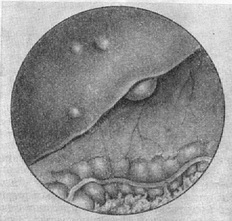

![]() Рис. 3. Передній край печінки (метастази раку).  |

При лапароскопії доступні огляду передній край печінки (рис. 3), дно жовчного міхура, передня стінка шлунка, великий сальник, товстий і тонкий кишечник, тазові органи. Неувеличенная селезінка не видно.